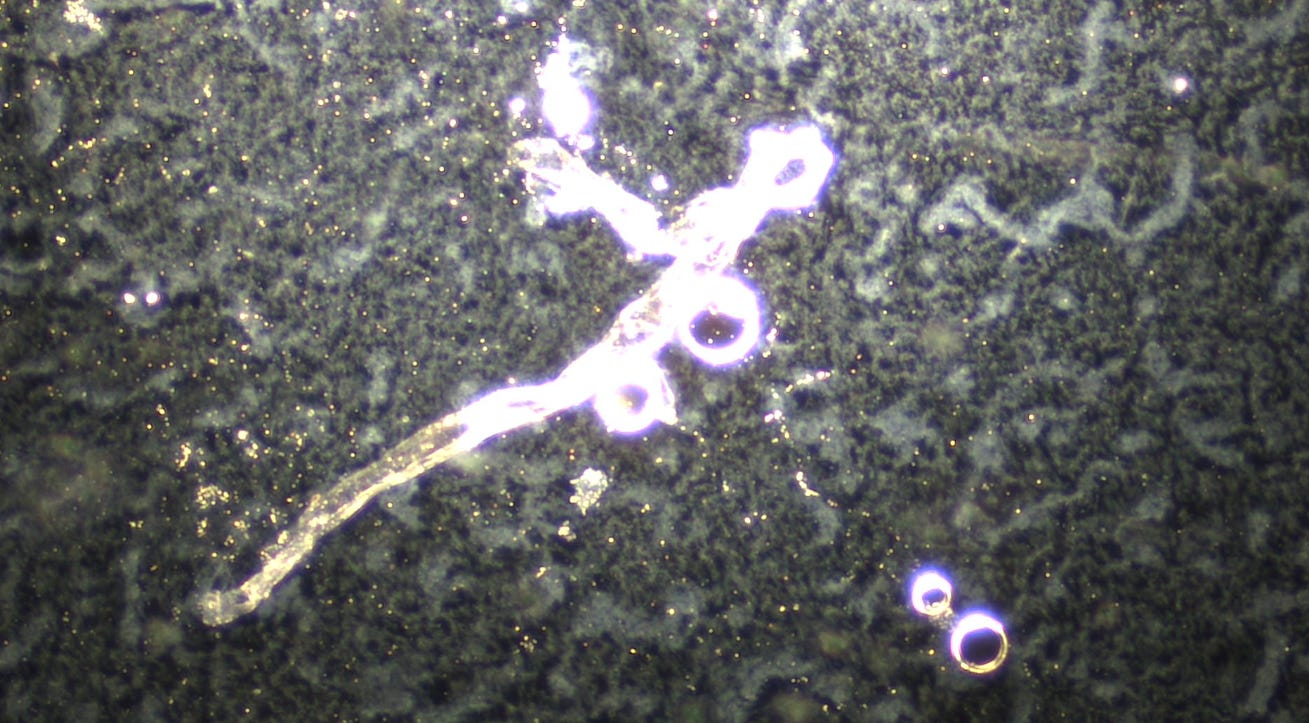

Image: Lantus Insulin mixed with Methylene Blue left overnight After seeing how well Methylene Blue works to prevent the rubbery clot formation, I wanted to test it with the different medications in which I have previously found the hydrogel. I used expired Methylene Blue 1 drop and a drop of Lantus Insulin for this testing.

I had shown before that Lantus has extensive Quantum Dots and hydrogels in it. You can review the Microscopy here: Darkfield Microscopy of Lantus and Humalog Shows Self Assembly Hydrogel I looked at Lantus Insulin first without Methylene Blue. Classic hydrogel background and filament construction was seen.

When I left the slides overnight, the Lantus had created chip like structures, similar to what we have seen in the dental anestetics:

Some microneedle crystals developed.

I left the slides overnight. The hydrogel had migrated around the Methylene Blue under the cover slip, as if it was magnetically attracting it.